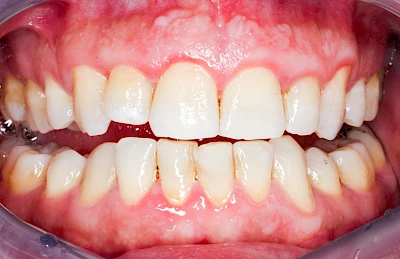

Ist zunächst nur das Zahnfleisch von der Entzündung betroffen, spricht man von Gingivitis. Später, wenn auch der Knochen um die Zähne herum entzündet ist, spricht man von einer Parodontitis. Bei der Parodontitis wird der Knochen nach und nach abgebaut und das Zahnfleisch zieht sich zurück. Die Zahnhälse und Zahnwurzeloberflächen liegen mehr und mehr frei. Die Zähne werden zunehmend lockerer und fallen schließlich aus.